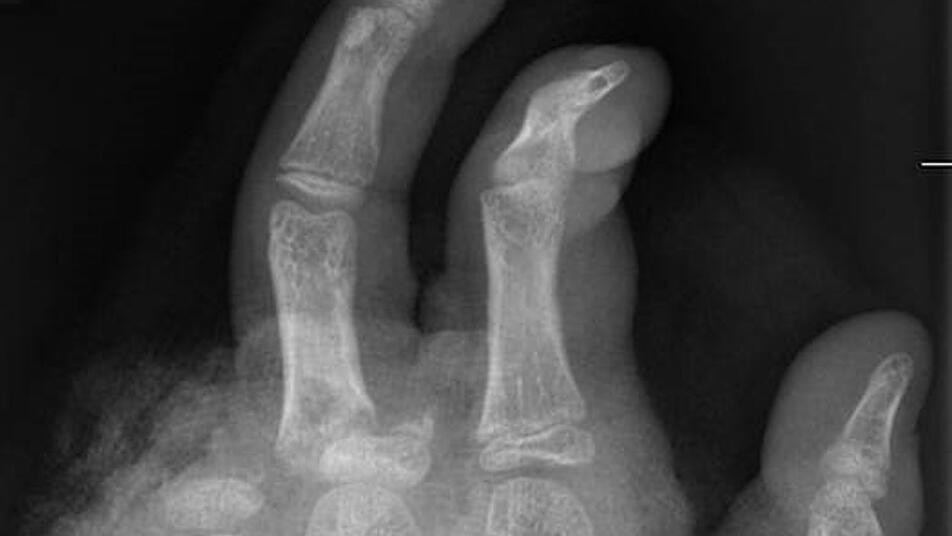

In der Handchirurgie müssten an Silvester im Unfallkrankenhaus rund 20 bis 40 Menschen mit Böllerverletzungen operiert werden, sagt die Ärztin. Dieses Jahr werde sie mir vier weiteren Handchirurgen im Einsatz sein. Die häufigsten Verletzungen entstünden durch explodierende Böller in der Hand.

«Der überwiegende Teil der Verletzungen trägt tatsächlich lebenslange Folgen mit sich, weil die Sprengkraft dazu führt, dass eben nicht nur einzelne Strukturen verletzt sind, sondern immer mehrere. Und das heilt praktisch nie ganz folgenlos ab.» Zum Teil könnten Hände nicht mehr gerettet und müssten amputiert werden.